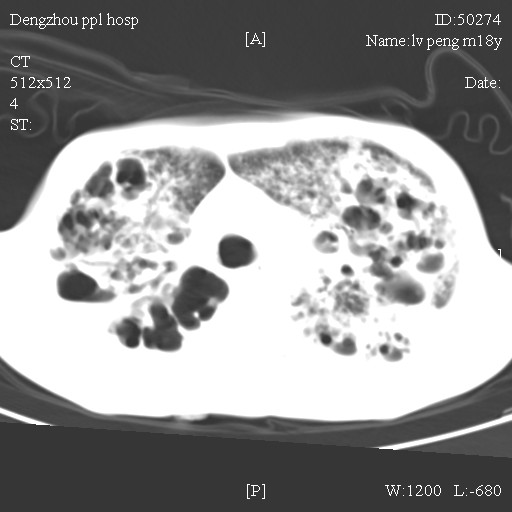

标题: CT10510:男.18岁,咳嗽咳痰两月.(有病理) [打印本页]

标题: CT10510:男.18岁,咳嗽咳痰两月.(有病理)

双肺布满大片状实变及网格状结节影,内参杂大小不等的气囊及空气支气管征,心脏增大。考虑:1 全身结缔组织疾病—系统性红斑狼仓?2 肺泡蛋白沉积症合并感染!

双肺布满大片状实变及网格状结节影,内参杂大小不等的气囊及空气支气管征,双侧胸膜腔少量积液,双下肺近膈面透亮度尚可,病人较年轻,病变较重(不知为什么上胃管?)考虑:1.胶原病肺部改变,2.组织细胞病x。结合实验室检查。

首先考虑组织细胞x病。两肺中上肺野多发囊腔,中下肺野内见多发小结节,并可见肺间质增厚。患者是男性,年龄较小。胶原性病变比较多见的类风湿、系统性红斑狼疮和硬皮病临床和影像均不是很支持,类风湿和系统性红斑狼疮的肺部表现最常见的是胸腔积液,硬皮病可见食管的扩张。

肺内多发斑片状、结节状、融合大片状及网格状影,多发薄壁空腔影,胸膜肥厚,纵隔、气管右移,考虑ⅲ型肺结核,多发空洞,继发肺间质纤维化。

双肺结核并播散.患者以肠梗阻入院,手术为肠结核.术后咳嗽做ct检查.